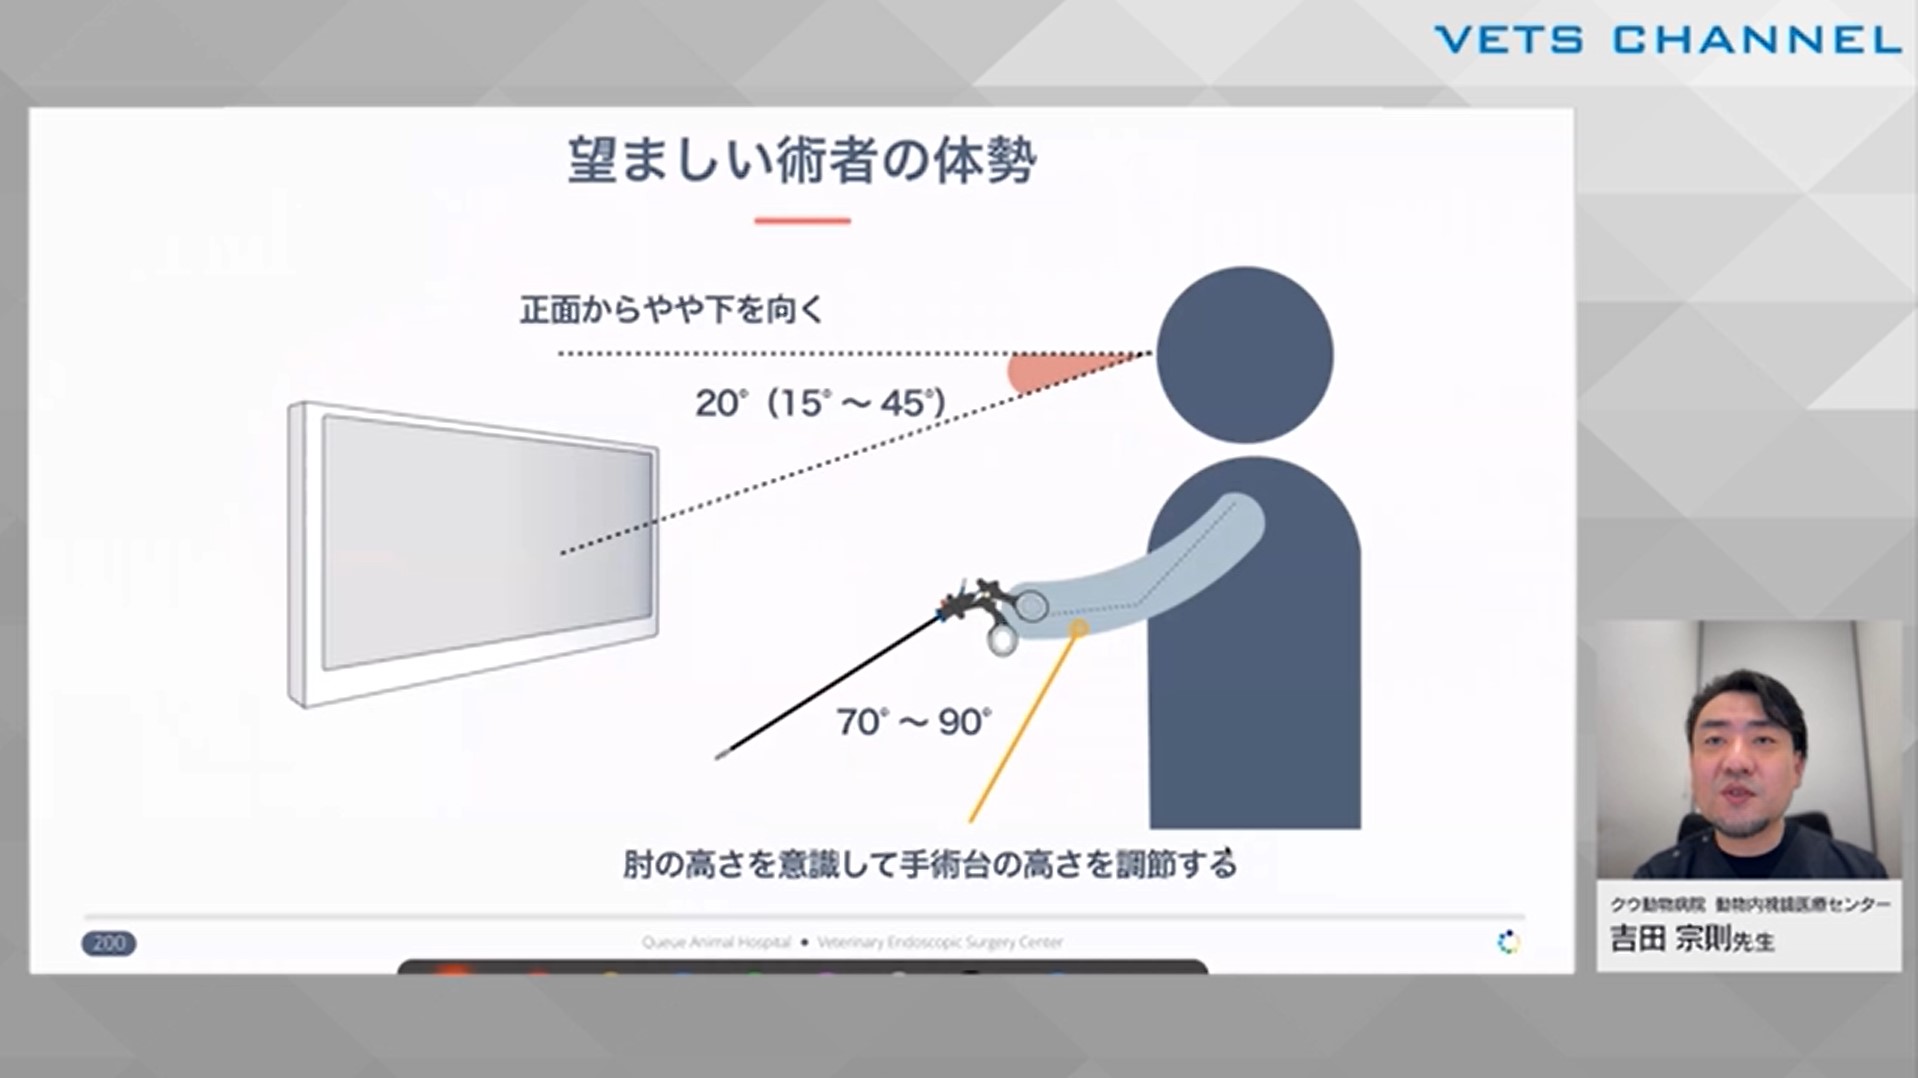

初学者のための腹腔鏡テクニック 第4回:「円滑な手術を実施するために」

- テクニック

- 内視鏡科

吉田 宗則先生(クウ動物病院 動物内視鏡医療センター)

46分

2025/01/03

初学者のための腹腔鏡テクニック 第1回:「腹腔鏡手術を始める前に」

- テクニック

- 内視鏡科

- 特殊器具が必要

吉田 宗則先生(クウ動物病院 動物内視鏡医療センター)

60分

2025/01/03